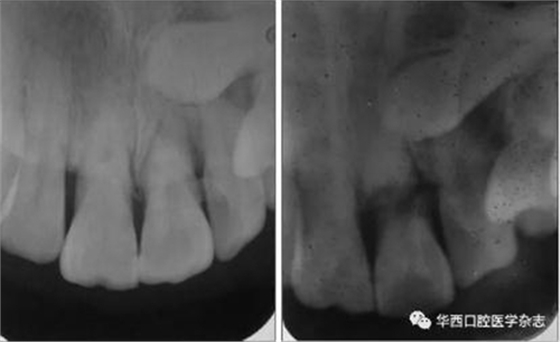

(1)變換角度X線投照的必要性。有些冠根折在行正常角度攝片時(shí)不易被發(fā)現(xiàn),變換角度再次攝片則可能被發(fā)現(xiàn)(圖1)。

左:未見根折;右:可見根折。

圖 1 21變換X線投照角度根尖片